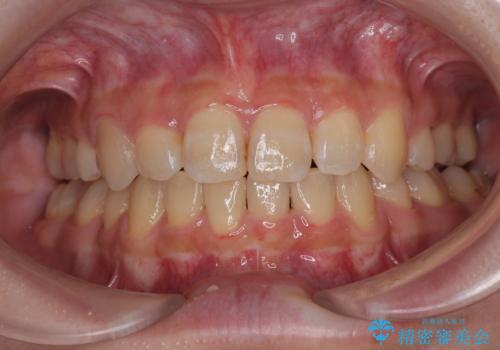

全顎的なデコボコと口元の突出感 ワイヤー装置での抜歯矯正で整った口元に